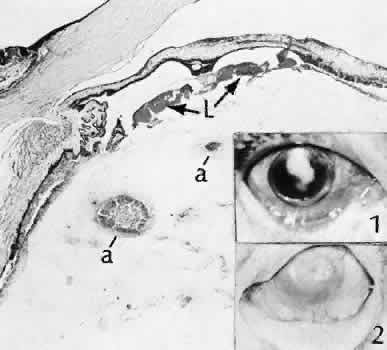

| No two eyes are traumatized in an identical manner.156–158 In contrast with surgical trauma, extremevariability and unpredictability

are the hallmarks of accidental trauma to the eye. Multiple types